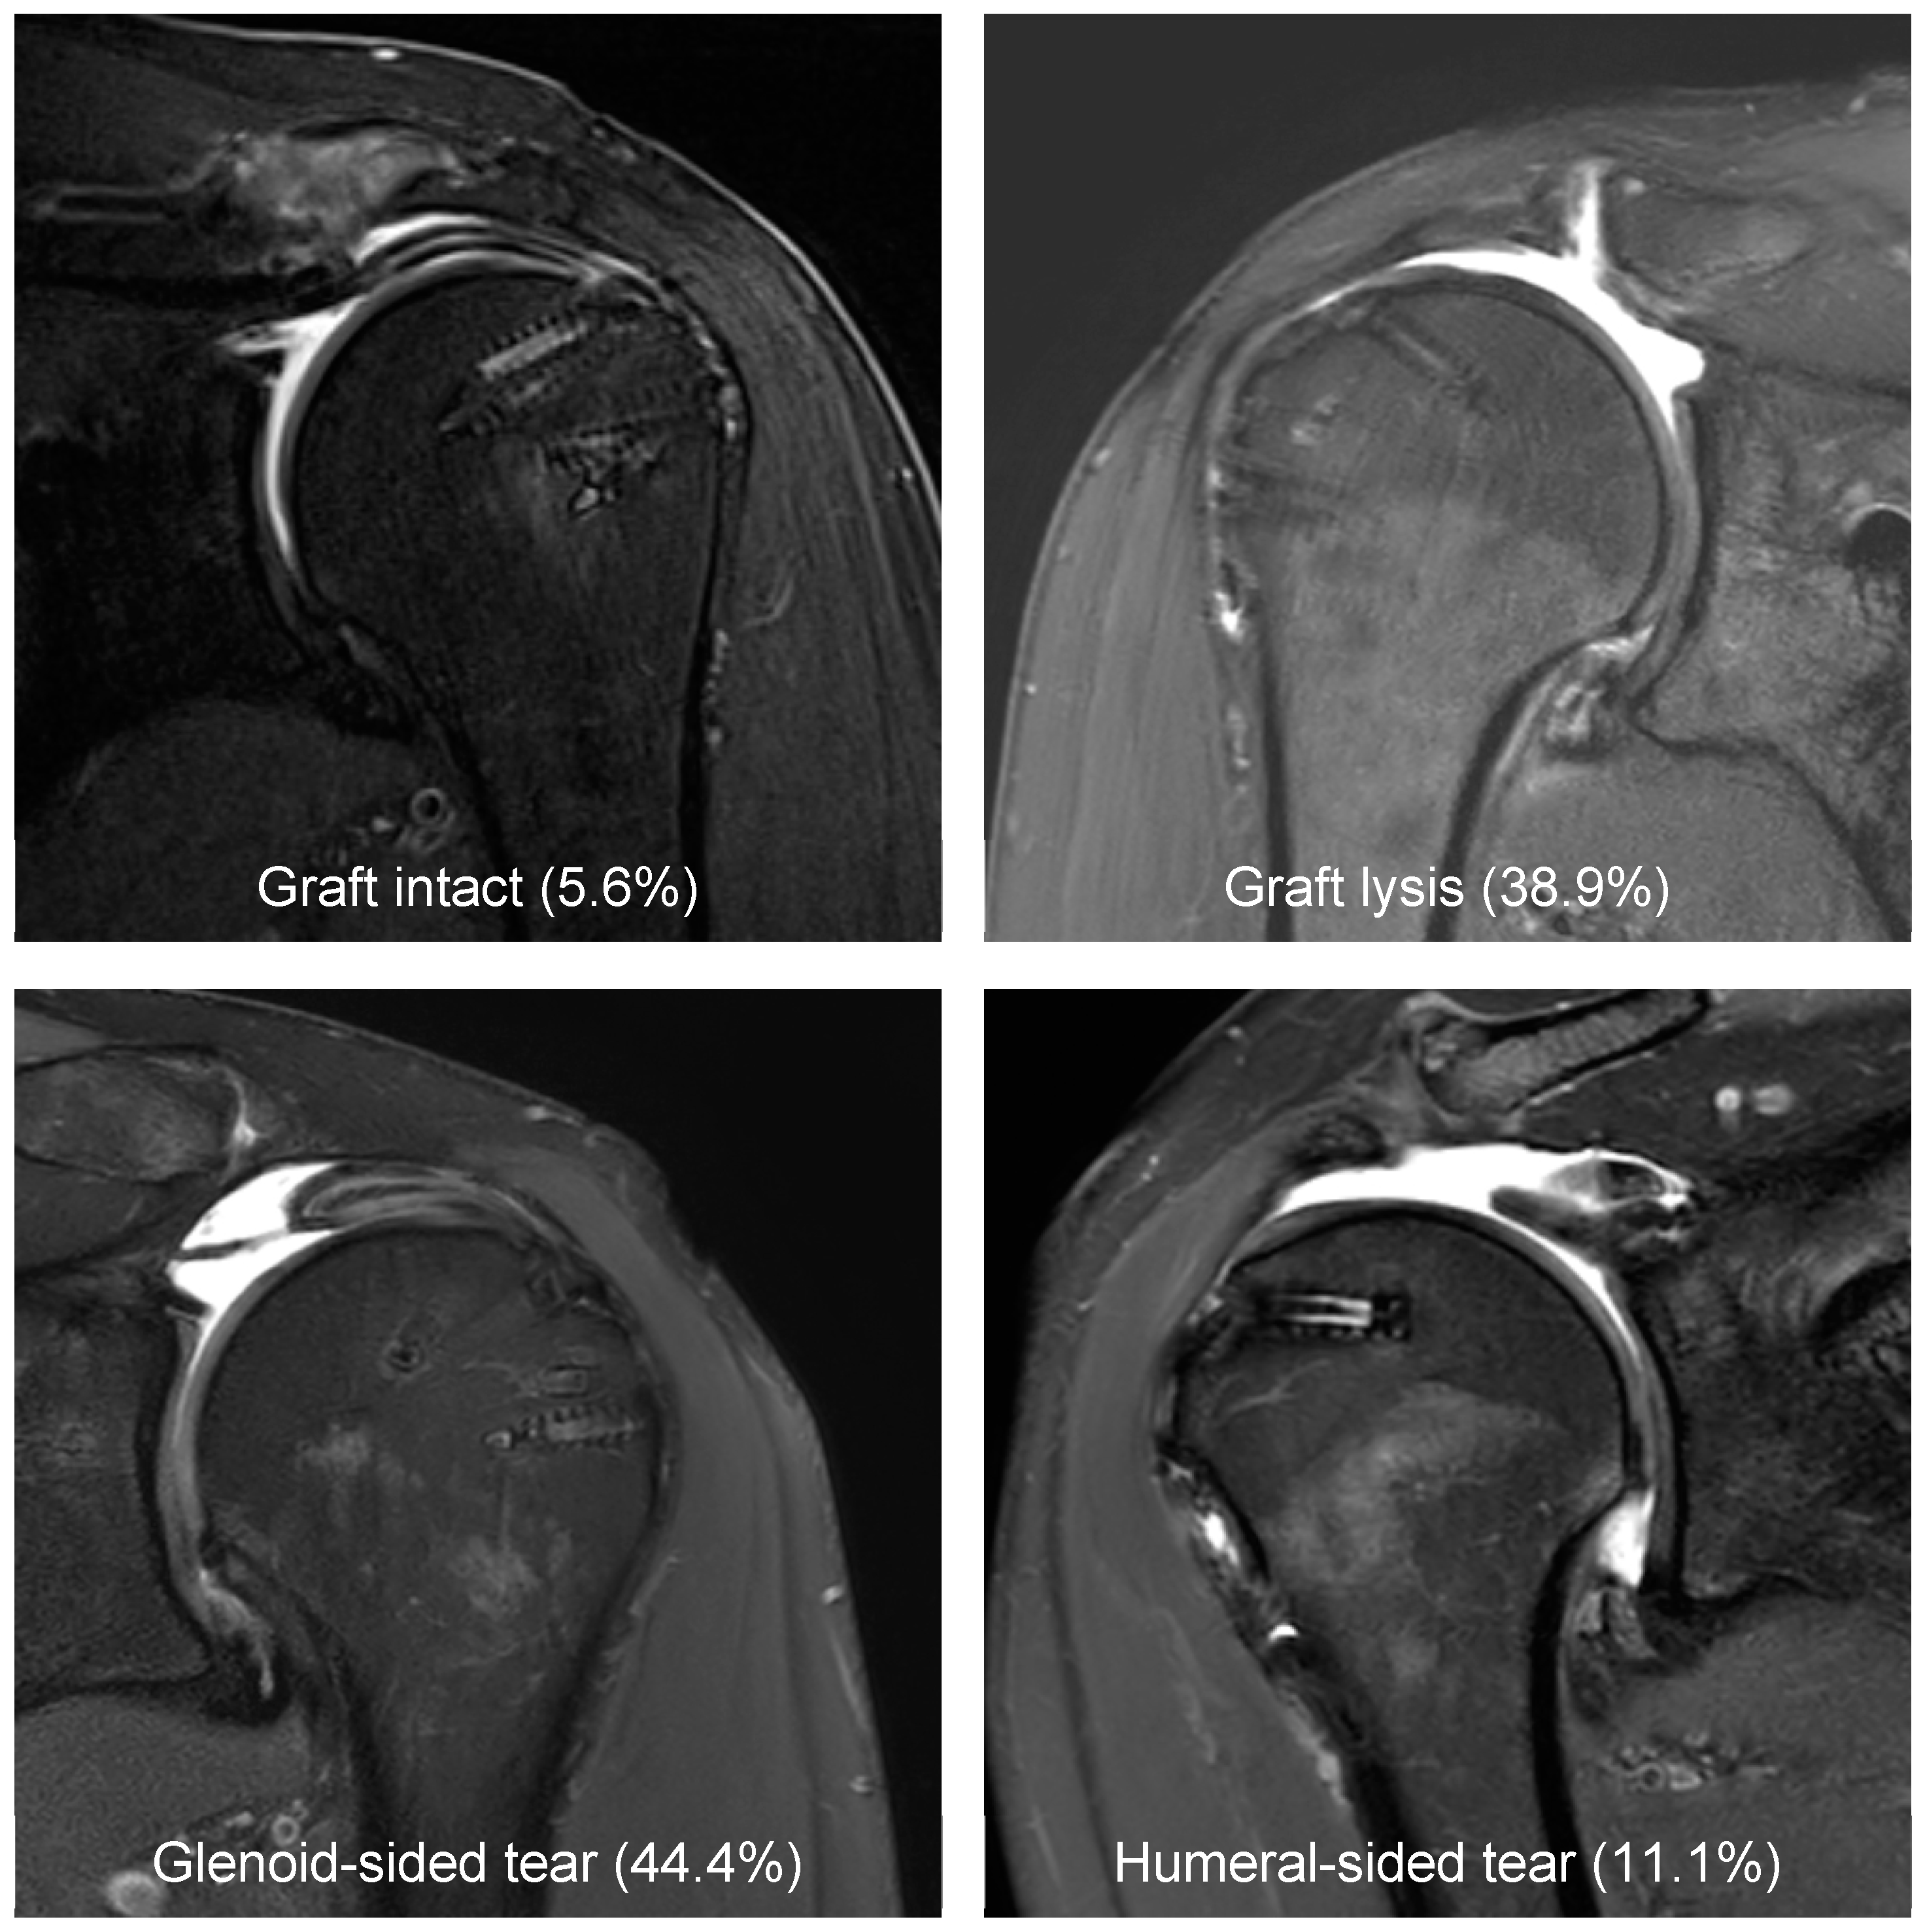

3.2. Radiological Outcome

- Mirzayan, R.; Acevedo, D.C.; Sidell, M.A.; Otarodi, K.A.; Hall, M.P.; Suh, B.D.; Singh, A. Classification System of Graft Tears Following Superior Capsule Reconstruction. Clin. Imaging 2022, 83, 11–15. [Google Scholar] [CrossRef]

- Shin, S.J.; Lee, S.; Hwang, J.Y.; Lee, W.; Koh, K.H. Tear Pattern after Superior Capsular Reconstruction Using an Acellular Dermal Matrix Allograft. J. Shoulder Elb. Surg. 2022, 31, e279–e288. [Google Scholar] [CrossRef] [PubMed]